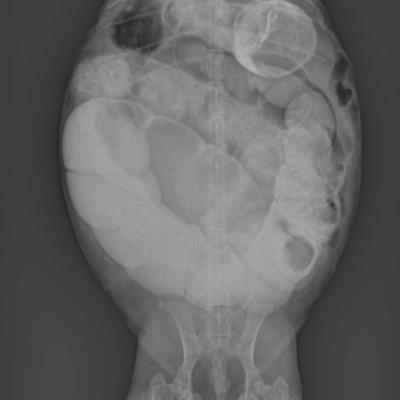

Colon de Lapin surchargé

Oeufs de Tortue